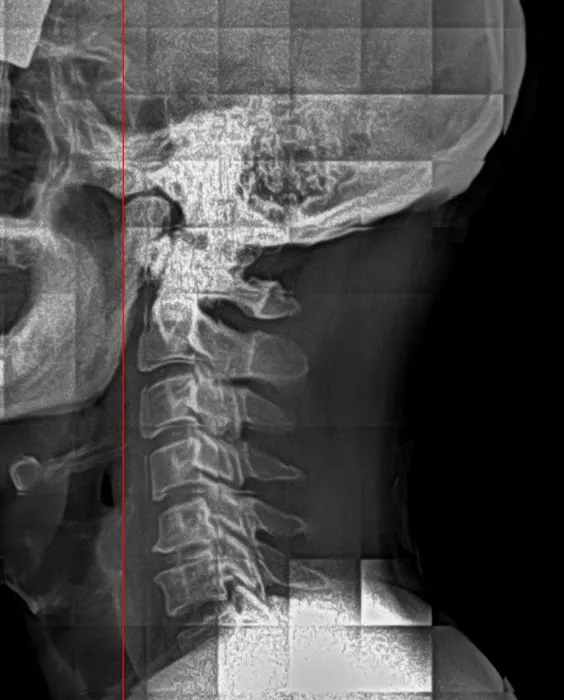

Chiropractic care is a widely recognized healthcare discipline focused on the diagnosis, treatment, and prevention of musculoskeletal disorders, particularly those affecting the spine. The foundational principle of chiropractic revolves around the idea that the body has an innate ability to heal itself, and that proper spinal alignment is crucial for optimal nervous system function. When the spine is misaligned, often referred to as a subluxation, it can interfere with nerve signals, leading to pain, discomfort, and various health issues. Through precise manual adjustments and other non-invasive techniques, chiropractors work to correct these misalignments, restoring the body's natural healing capabilities. Many New Jersey residents turn to chiropractic care not just for pain relief, but also for improved athletic performance, better posture, and overall enhanced well-being. It’s a holistic approach that seeks to address the root cause of issues, rather than simply masking symptoms.

- **Spinal Adjustments and Manipulations:** The core of chiropractic care, these gentle and specific adjustments help correct spinal misalignments, reduce nerve interference, and restore proper bodily function, leading to relief from various forms of pain.

- **Pain Management for Back & Neck:** Specializing in both acute and chronic pain in the back and neck, Dr. Dan employs various techniques to identify and alleviate the underlying causes of discomfort, offering lasting relief.

- **Sciatica Treatment:** Providing targeted care for the often debilitating pain associated with sciatica, focusing on reducing pressure on the sciatic nerve and restoring spinal alignment to mitigate symptoms that can radiate down the leg.

- Digital X-Rays